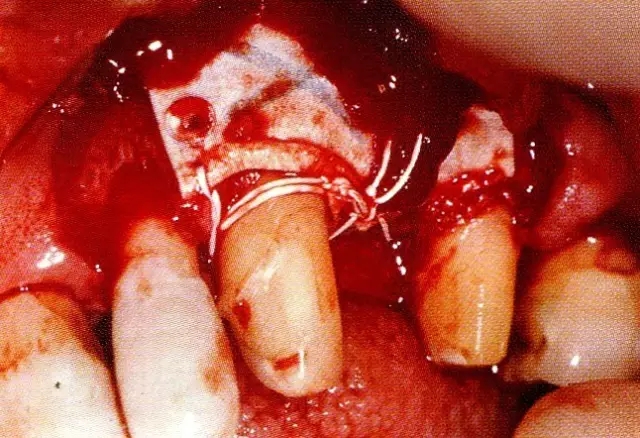

640.webp (2).jpg

▲圖7-3  將posterior interproximal類型的非吸收性覆膜修整后進(jìn)行垂直懸吊縫合做固定。垂直懸吊縫合后,確定覆膜是否會(huì)動(dòng)搖,再將齦瓣與之緊密縫合。